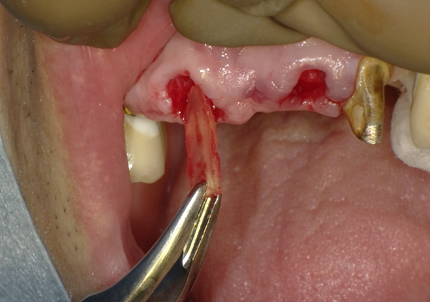

11.舌側歯牙片の抜歯

【右上1番SST 口蓋側歯根の抜歯】

【左上2番 SST 口蓋側歯根の抜歯】